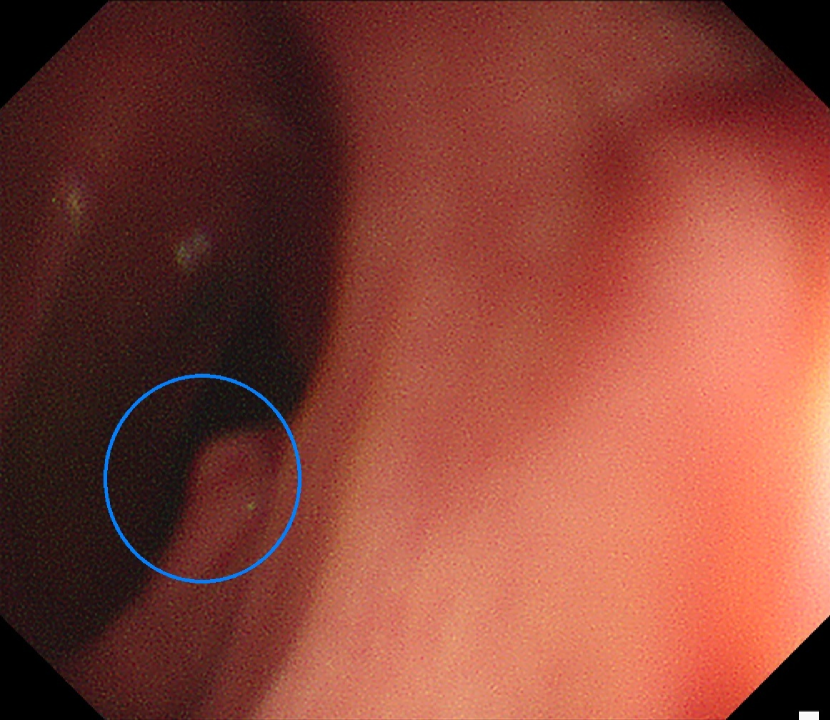

Refer to caption

(d)

Figure 7: Sample images from the testing dataset, with results from the best performing model. White boxes are the ground truth annotations, blue ellipses are the model predictions. In the first row, examples of false negative polyps are shown: (7(a)) a small and distant polyp, (7(b)) a polyp partially covered by water/bubbles, (7(c)) a polyp framed in blue light, (7(d)) a large polyp near the image boundary and overexposed. In the second row, examples of false positive detections are shown: (7(e)) the model activates on a artifact due to stain and motion blur, (7(f)) the model activates on a solid residue, (7(g)) the model activates on an area of the colonic mucosa that is not well inflated, (7(h)) the model activates on a dark and distant area of the colonic mucosa whose shape is similar to a polyp.

Finally, in Figure 7, we display examples of false negatives and false positives from the test set, generated by the best performing model. To visually assess the performance on a whole video, we have uploaded a 60-minute colonoscopy video featuring 6 polyps, the longest in our test set, at https://figshare.com/s/fbb0834a21082984336c (with predictions marked in cyan and ground truth boxes in white). The image examples illustrate how the model struggles with small, occluded, or poorly imaged polyps, and generates false positives in areas that visually resemble polyps, often due to motion or suboptimal imaging. These observations persist throughout the entire video analysis, highlighting the importance of minimizing false positives throughout the entire procedure while maintaining high polyp recall.